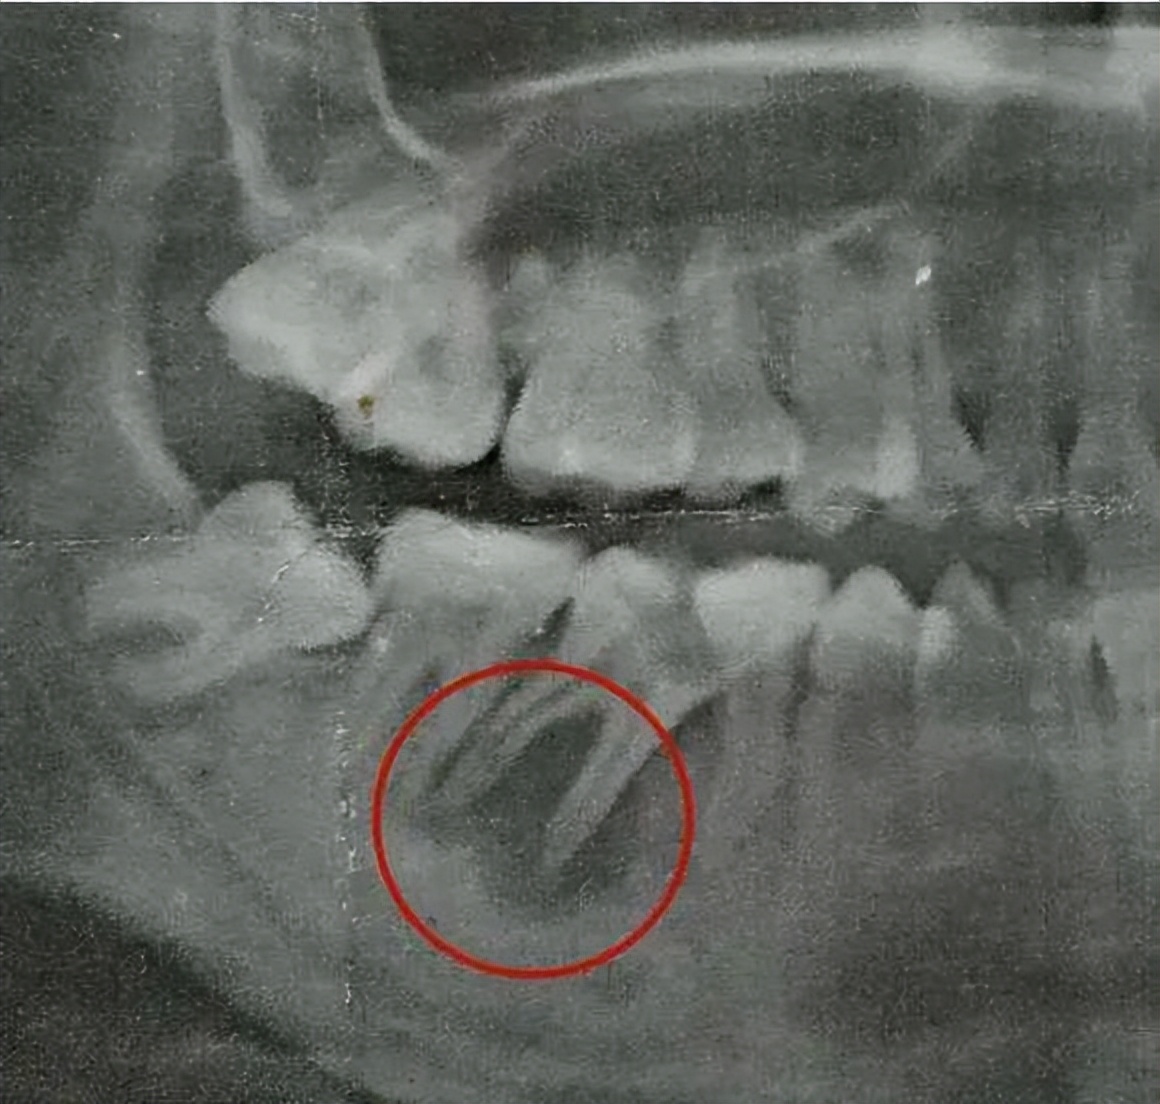

一般情况下,牙齿龋坏严重、严重的牙齿隐裂引起牙髓坏死,出现炎症以及根尖炎症并且无法进行保髓治疗的情况需要进行根管治疗。

一般情况下,口腔科医生经过检查后评估确认是需要进行根管治疗的话,建议要进行治疗,如果不治疗的话,引发的根尖炎症容易影响牙槽骨组织,影响其他健康牙齿,情况严重的还会造成囊肿、骨髓炎等。因此如果医生建议进行根管治疗的话,还是尽量及早治疗。